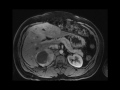

Pheochromocytoma

MRI images demonstrate a hypervascular right adrenal mass with central necrosis , found to be a pheochromocytoma.